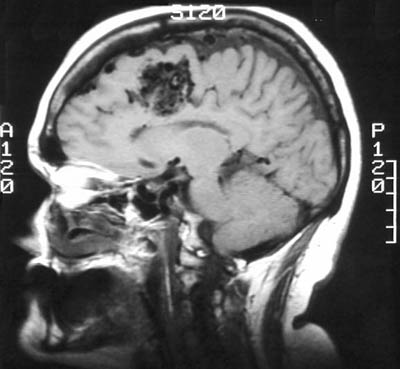

There is a vascular malformation in the right medial frontal lobe, as seen above in sagittal view with T1 weighted MRI scan. The lesion is seen below in axial view with T1 and T2 weighted MRI scans. Note the large, irregular vascular channels.